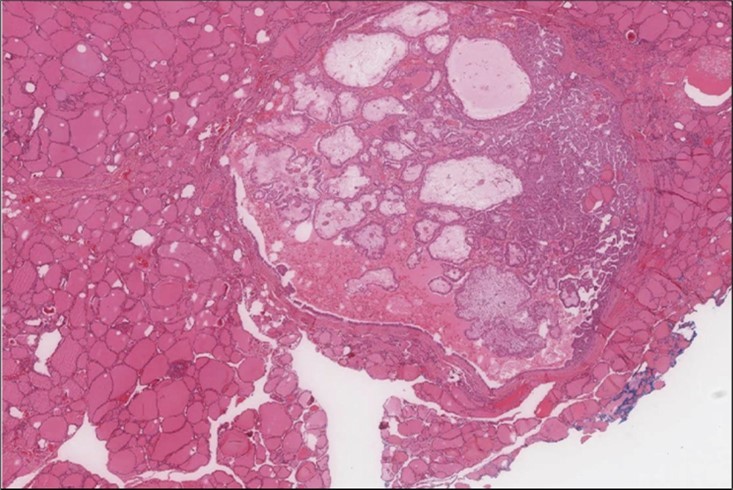

Figure 5.Liver biopsy Lower power of the liver core showing normal liver and part of the metastatic foci (H&E, x4)

Figure 6.Liver Biopsy Higher power showing the metastatic foci is almost identical to what is seen in the thyroid with the highly atypical spindle cells. (H&E, ×200).

cancer, or other metastatic tumors without further testing with genetic or molecular studies 3, 7. Immunohistochemical testing plays a vital role in differentiating LMS from such similar tumors as it stains positive for vimentin and smooth muscle actin (SMA), and is variably positive for HHF35, desmin (50%-100%), and H-caldesmon 3, 6. Moreover, there were no reported cases where thyroid LMS stained positive for thyroglobulin, cytokeratin, calcitonin, chromogranin, or protein S100 3. Our patient’s left thyroid biopsy showed the characteristic microscopic features and was positive for SMA, desmin, caldesmon, P63 with patchy EMA (Figure 1, Figure 2, Figure 3, Figure 4) as well as her liver biopsy (Figure 5, Figure 6, Figure 7); whereas her right thyroid showed clear papillary thyroid cancer cell features (Figure 8, Figure 9).